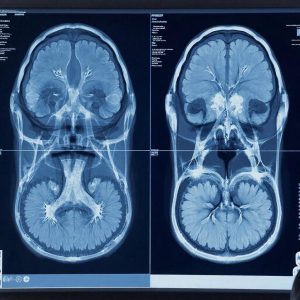

Магнитно-резонансная томография (МРТ)

📝 МРТ основана на использовании мощного магнита и радиочастотных волн, создавая подробные трехмерные изображения мозга. Она особенно эффективна при выявлении небольших зон повреждения ткани мозга, которые могут остаться незамеченными на КТ.

Исследования показывают, что МРТ значительно превосходит КТ в обнаружении ранних признаков инсульта, обнаруживая патологические изменения уже спустя считанные минуты после события.